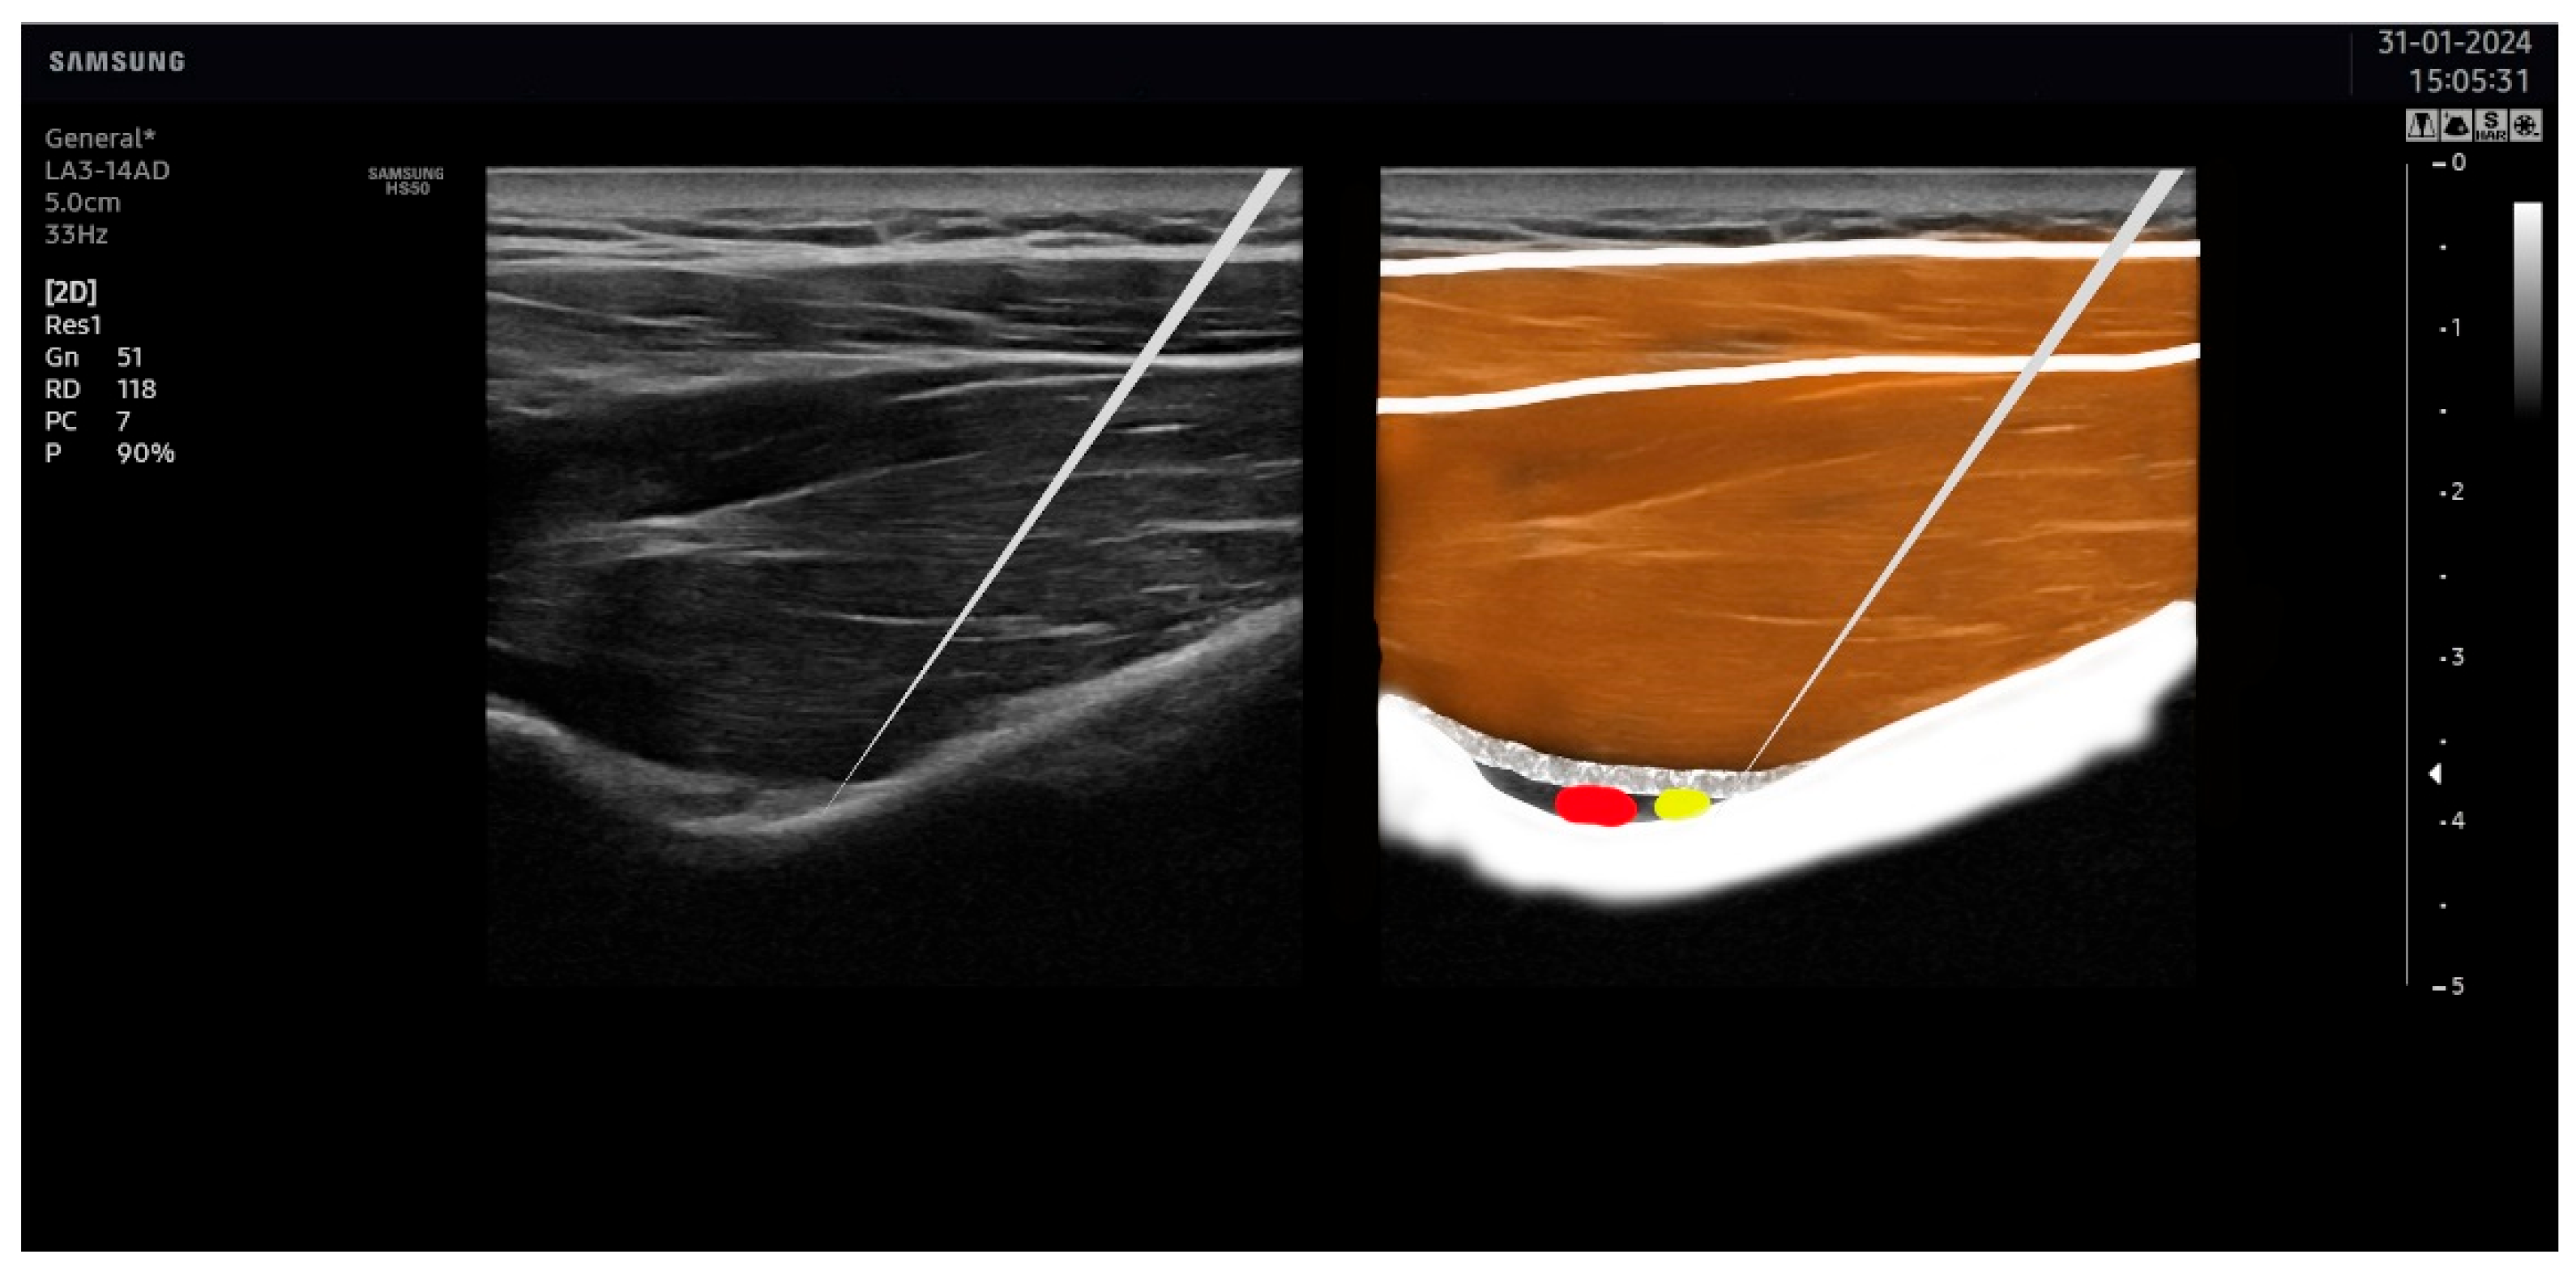

2.5. Ultrasound-Guided Percutaneous Nerve Stimulation

2.6. Placebo Ultrasound-Guided Percutaneous Nerve Stimulation